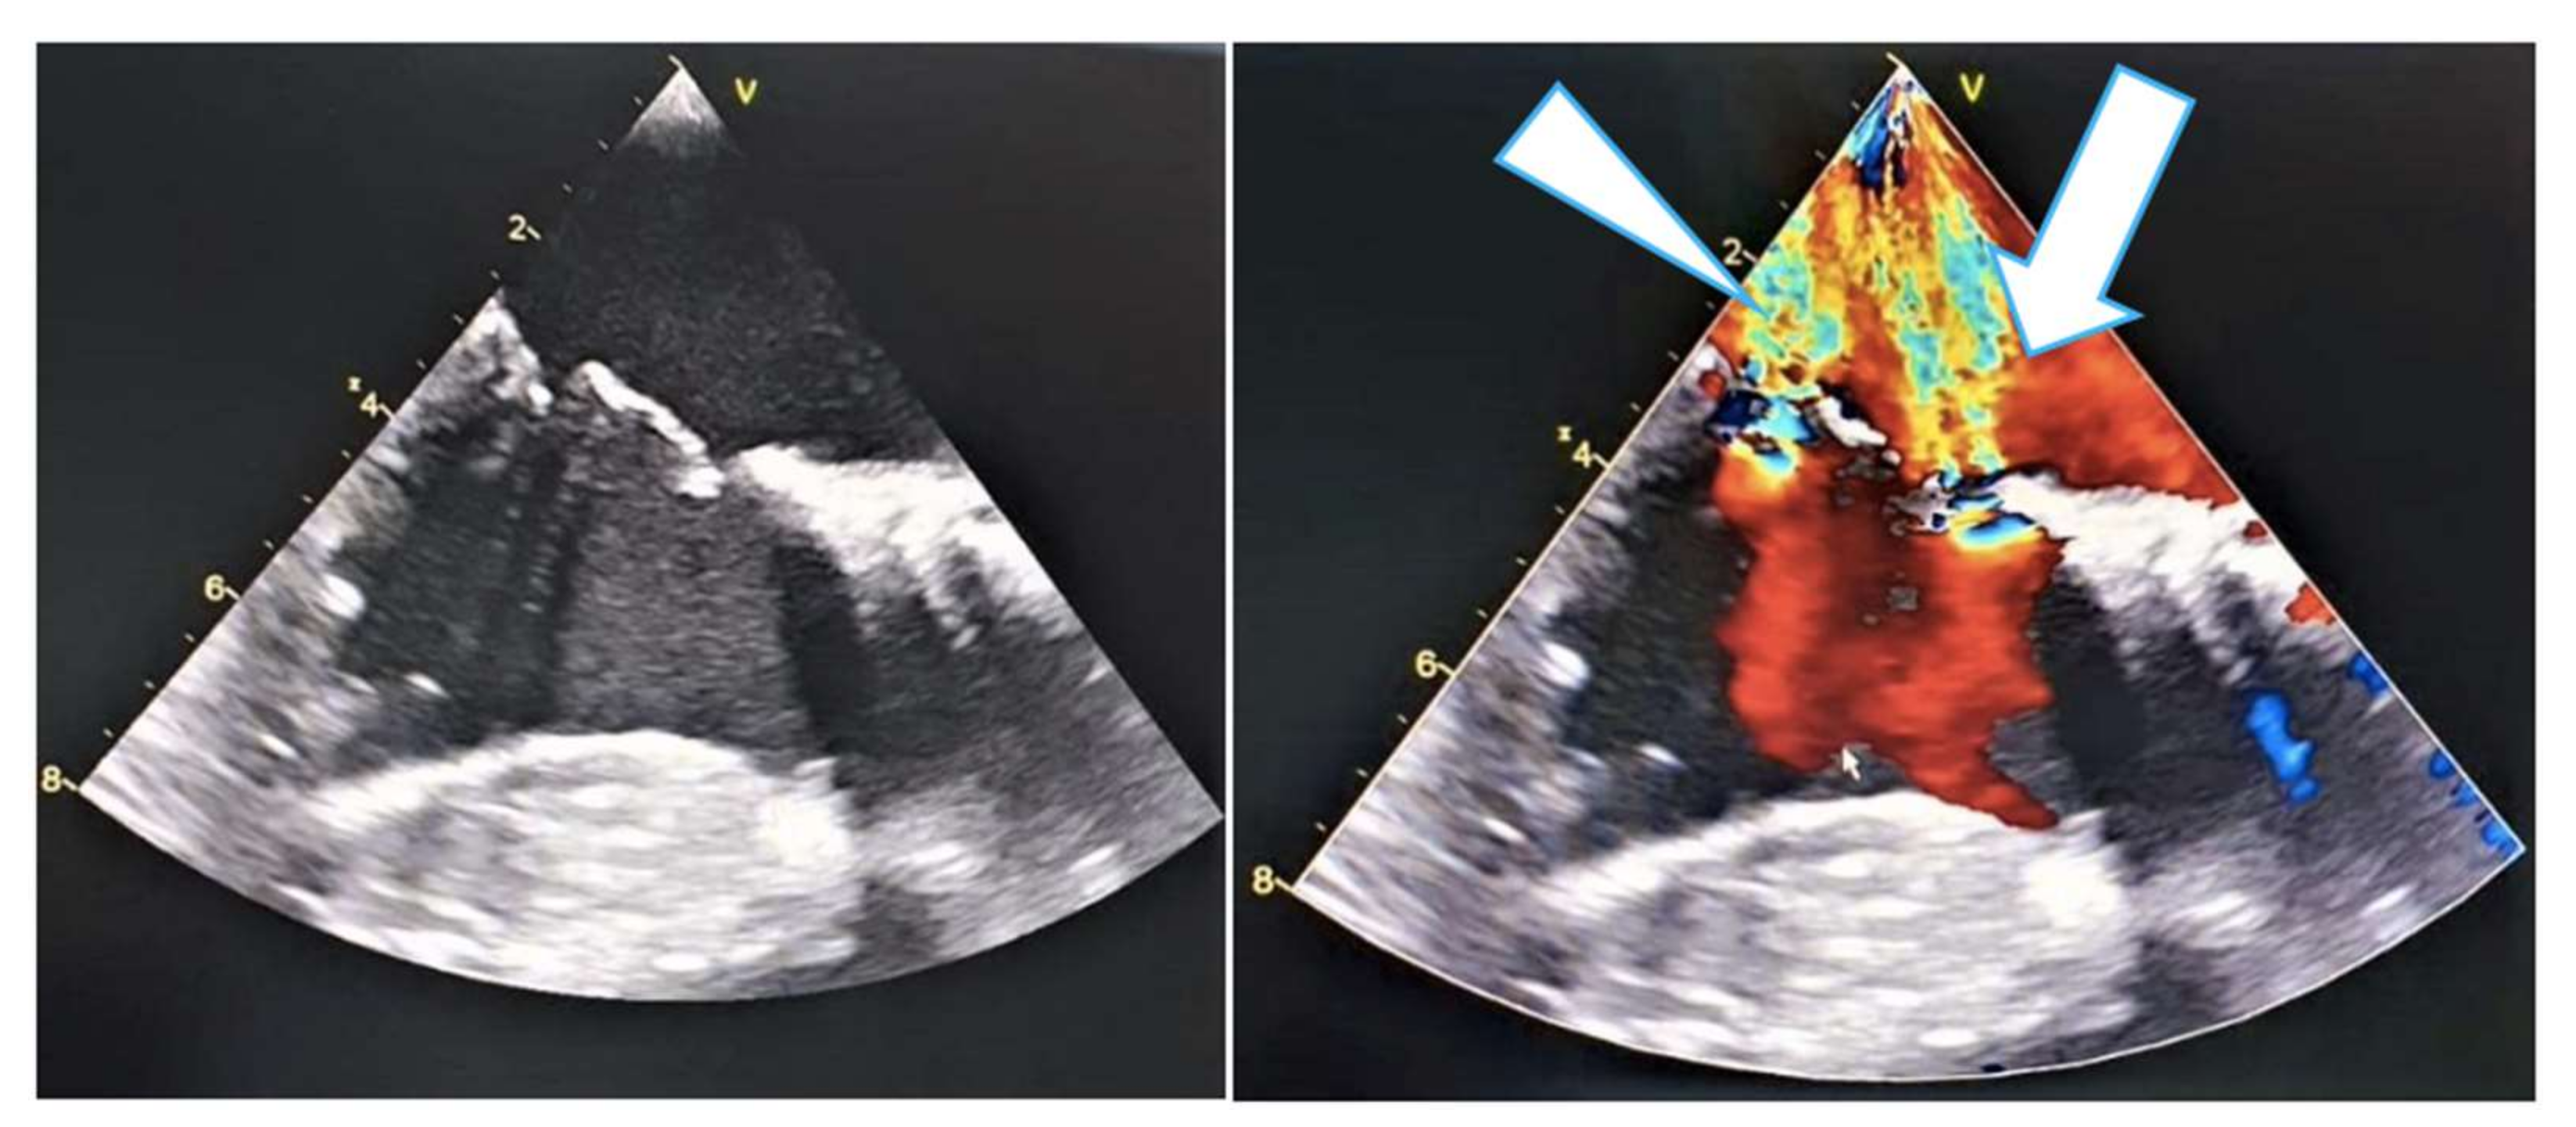

2. Case Report